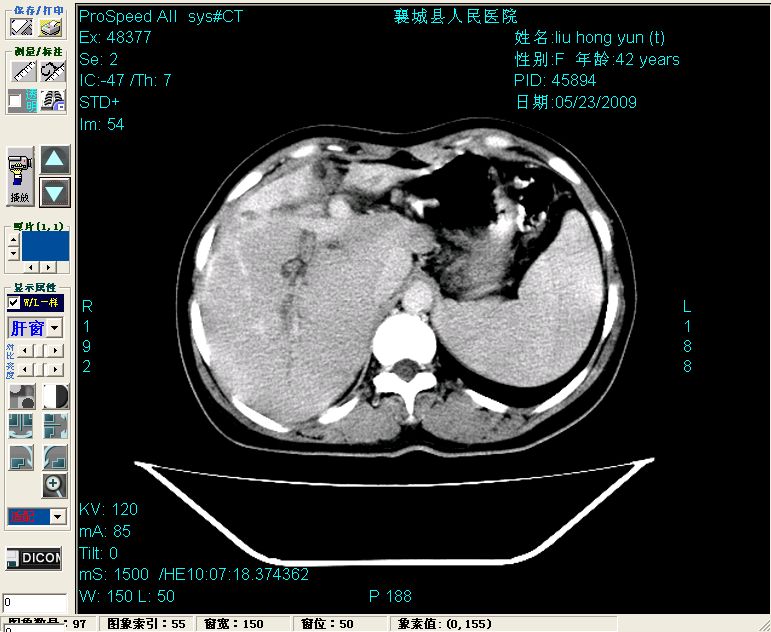

平扫:

平扫左肝外叶体积显著减小,左肝外叶见多房囊性低密度区,左肝实质及右肝前叶浅表实质呈低密度改变,左肝及右肝前叶胆管扩张,脾大

增强动脉期前述低密度区轻度早其强化,门脉期强化程度显著增高,延期扫描强化程度下降,但仍为相对高密度影

胰头部见结节状高密度影,其前方略可分辨扩强胆部管,平扫到增强始终有,但现在尚难与胃肠造影剂鉴别.

结合病史考虑,1现在引起黄疸体征的原因应该是胆总管胰段结石阻塞,建议局部胃肠造影剂排空后复查.

2左肝及右肝前叶表现考虑胆囊摘除术后所致的肝动门脉瘘形成,慢性纤维组织炎性增生.不完全除外左肝胆管细胞癌

3脾大,可能与动门脉瘘所致门脉高压有关